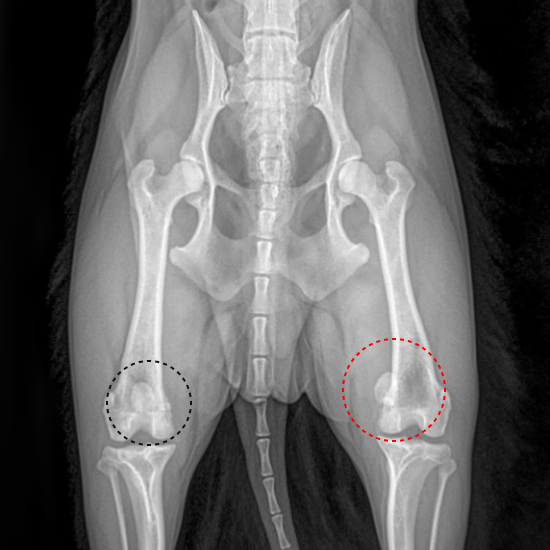

실제 엑스레이 이미지를 보시면,

왼쪽 검정 동그라미 속의

슬개골은 뼈 사이에 얌전히 잘 있습니다.

하지만 오른쪽의 빨간 동그라미의 슬개골은

뼈 안이 아닌 바깥쪽으로 튀어나온 상태

즉 슬개골이 탈구된 것입니다.

3~4기는 위의 엑스레이 이미지처럼

항상 빠져있으므로 엑스레이를 통해 발견됩니다.